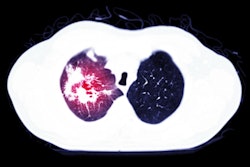

During the same ECR session, Prof. Johny Verschakelen, professor of radiology at the Catholic University of Leuven in Belgium, outlined the numerous challenges of differentiating between honeycombing and paraseptal emphysema.

On CT, both entities appear as millimetric to centimetric lucent spaces, but while honeycombing is surrounded by irregular coarse lines, paraseptal emphysema is surrounded by smooth, fine lines.

CT signs of honeycombing versus paraseptal emphysema. Courtesy of Prof. Johny Verschakelen.Furthermore, in honeycombing, multiple layers of these lucent spaces look like a reticular pattern, and they can be anywhere in the lung. In paraseptal emphysema, only one layer of lucent spaces can be seen, and these are always subpleural. This includes the subpleural fissure area, according to Verschakelen.

Honeycombing is often basal and peripheral but may extend to the middle and apex of the lung, and with this distribution, it is highly suggestive of usual interstitial pneumonia (UIP) in the setting of idiopathic pulmonary fibrosis (IPF). On the other hand, paraseptal emphysema is always apical and may extend to the middle and basal lung.

It is crucial to look at the clinical context, he continued. The presence of sometimes extensive honeycombing may indicate that the patient has chronic fibrotic interstitial lung disease.

"Honeycombing is a fibrotic process -- the result of extensive fibrosis with tissue destruction. This means that usually in addition to the honeycombing, you'll see some other small signs of fibrosis like lung deformation or traction bronchiectasis. The fibrosis usually induces functional impairment," Verschakelen said.

A patient with paraseptal emphysema could be a smoker or have chronic obstructive pulmonary disease, he added. Here, the process starts with tissue destruction and little fibrosis, and these patients don't always have functional impairment. Paraseptal emphysema may even be an incidental finding.

Location is the key when it comes to differentiating honeycombing from paraseptal emphysema. Courtesy of Prof. Johny Verschakelen.Verschakelen's top tip for differentiation of honeycombing and paraseptal emphysema is that radiologists should ask themselves two questions: Is there more than one layer and/or a reticular pattern? Is there fibrotic deformation with irregular borders or other signs of deformation? For both questions, a positive answer means that honeycombing is the most likely diagnosis. However, location is key. If hyperlucent spaces are limited to the upper part of the lung in the subpleural area, then paraseptal emphysema is more likely.